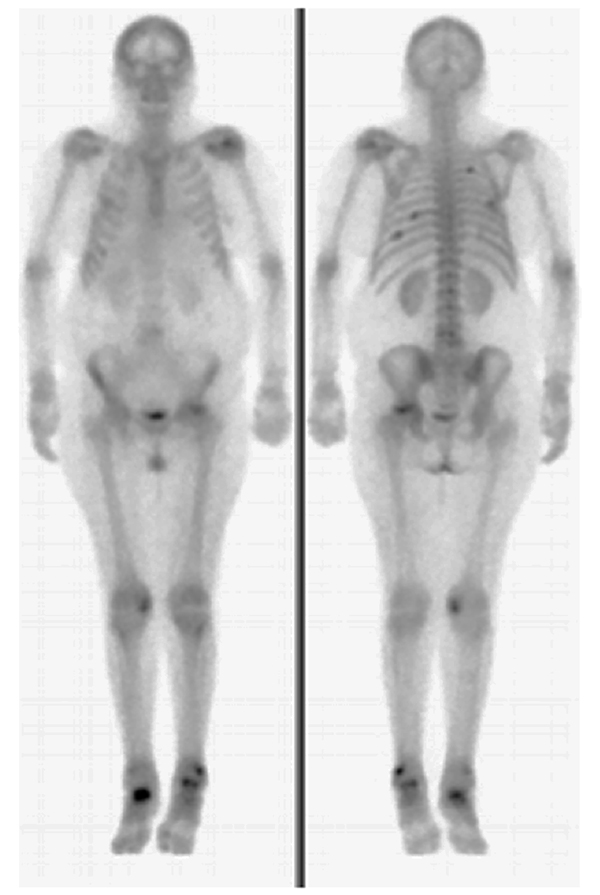

La gammagrafía ósea mostraba imágenes hipercaptantes a predominio del cóndilo femoral interno derecho y platillo tibial externo izquierdo (fig. 4).

Figura 4: Centellograma óseo, hipercaptación a predominio del cóndilo femoral interno derecho y platillo tibial externo izquierdo.